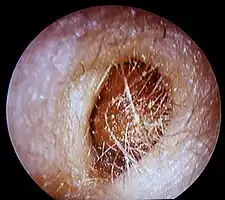

Conduit auditif externe gauche, au fond le tympan

Bouchon de cérumen complet dans le conduit auditif